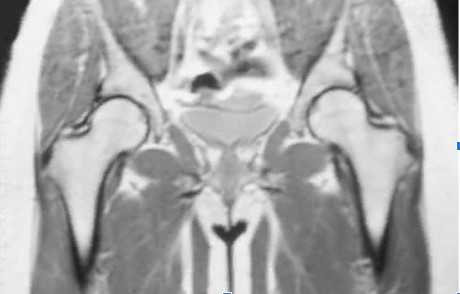

Асептический некроз головки бедренной кости на МРТ

МРТ - наиболее точный метод диагностики при подозрении на аваскулярный некроз головки бедренной кости. Исследование демонстрирует изменения на ранних стадиях патологического процесса, когда рентгенография, остеосцинтиграфия и КТ с контрастированием малоинформативны.

Магнитно-резонансное сканирование помогает определить размер поражения, оценить состояние суставного хряща и костного мозга, обнаруживает избыточное скопление жидкости в сочленениии. Для получения диагностически ценных снимков при остеонекрозе предпочтительнее сделать МРТ на высокопольном аппарате с закрытым контуром мощностью от 1,5 Тесла. Прочие сканеры недостаточно чувствительны для выявления аваскулярного некроза головки бедренной кости (АНГБК). Отсутствие ионизирующего излучения позволяет обследовать суставы без вреда для здоровья у беременных и детей в возрасте от 4 недель.

Как выглядит асептический некроз головки бедренной кости на МРТ?

МР-изображение АНГБК на сканах а, в соответствует I ст. заболевания, стрелки указывают на зону отека костного мозга; c, d - II ст., область омертвевшей ткани (стрелки); e, f - III ст., субхондральный вдавленный перелом (стрелки)